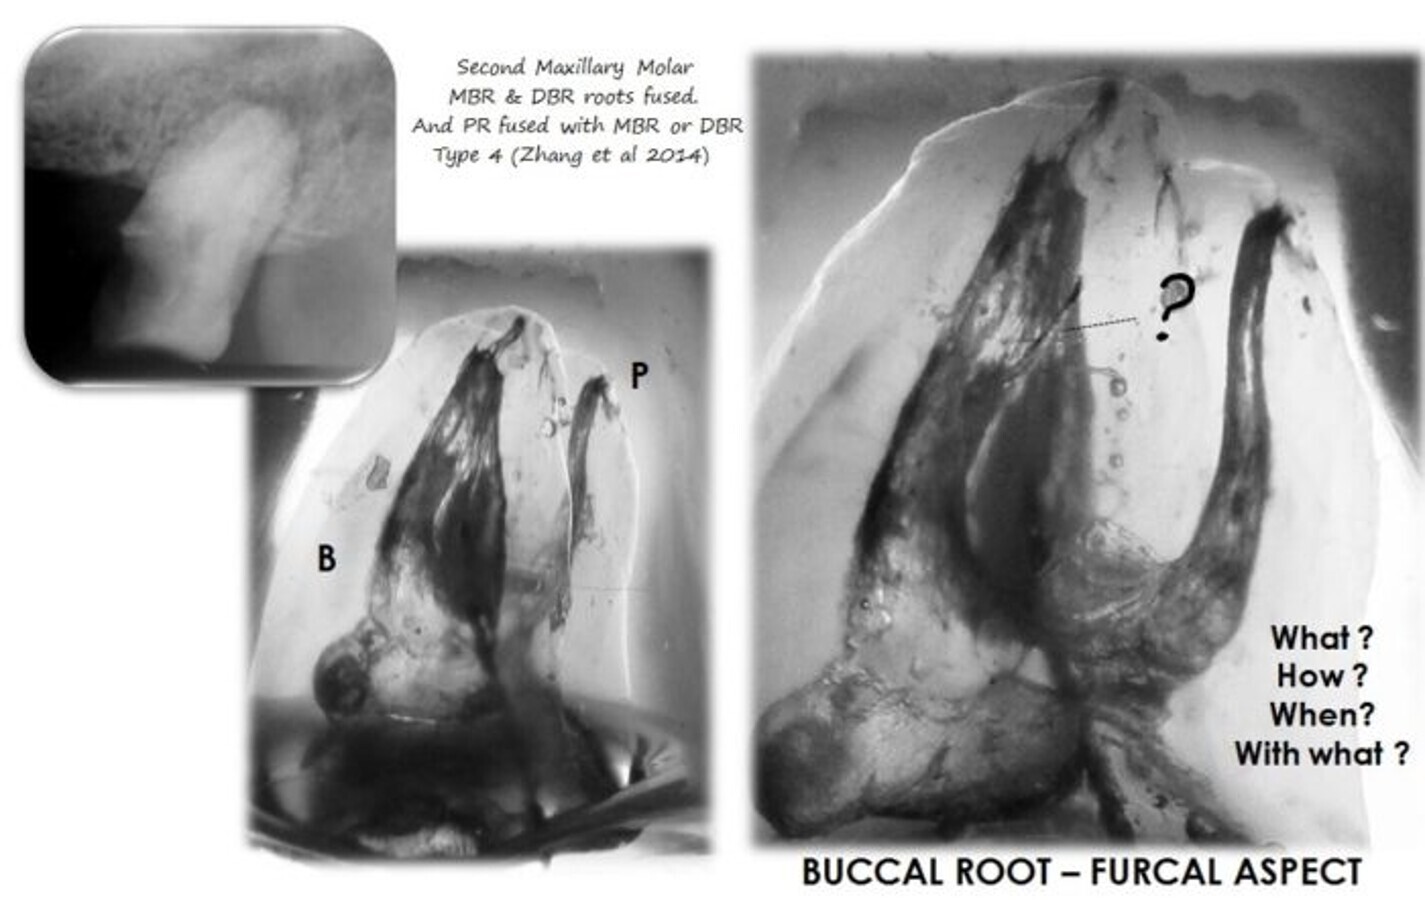

Cleared sample shows the complexity of a maxillary second molar with fused roots. (Image: Dr Sergio Rosler)

Maxillary second molars are always a challenge for root canal therapy. This difficulty is related to the location of the tooth, way back in the maxilla with...